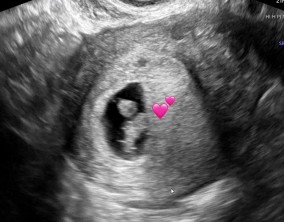

두 줄에서 심장소리까지, 따뜻하게 이어진 시간

이예흔 원장님을 비롯해 의료진과 선생님들 모두 친절하게 대해주셨고, 병원 전체 분위기도 따뜻해서 치료를 받는 동안 마음이 한결 편안했습니다. 그런 환경 덕분에 끝까지 치…